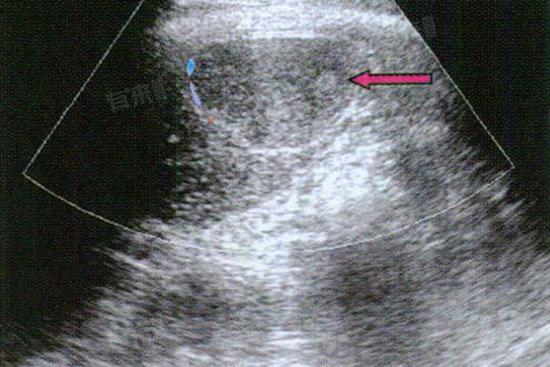

1、肝囊肿:这是形成肝右叶稍低密度灶的常见原因之一,肝囊肿是肝脏内出现的充满液体的囊性结构,多为先天性,生长缓慢且通常无明显症状。在CT或MRI影像上,表现为边界清晰、密度均匀的低密度影,内部液体成分使其密度明显低于周围正常肝组织,一般不需要特殊处理,定期观察即可。

2、肝血管瘤:作为肝脏常见的良性肿瘤,肝血管瘤由扩张的血管组成。在影像检查中,肝右叶的血管瘤呈现稍低密度,增强扫描后可见特征性的向心性强化。多数肝血管瘤生长缓慢,患者无不适症状,但较大的血管瘤可能压迫周围组织,需要根据具体情况决定是否进行干预。

3、肝脂肪浸润:当肝脏内脂肪过度沉积,会出现局部或弥漫性的脂肪浸润,在影像上表现为稍低密度灶。这种情况多与肥胖、饮酒、代谢综合征等因素相关,属于可逆性改变。肝右叶脂肪浸润区域的密度低于正常肝实质,通过改善生活方式和控制基础疾病,低密度灶可逐渐减轻甚至消失。

4、肝脓肿:肝脏受到细菌、真菌等病原体感染后,局部组织发生化脓性炎症形成脓肿。肝右叶脓肿在早期影像上呈现边界模糊的稍低密度灶,随着病情发展,病灶中心出现液化坏死。患者常伴有发热、肝区疼痛等症状,需要及时进行抗感染和引流治疗,避免病情恶化。

5、肝脏恶性肿瘤:原发性肝癌或转移性肝癌均可在肝右叶表现为稍低密度灶,这类病灶形态不规则,边界不清,增强扫描时强化方式与良性病变不同。恶性肿瘤生长迅速,会侵犯周围组织并发生转移,严重威胁患者生命健康,一旦怀疑恶性可能,需尽快完善检查明确诊断,制定治疗方案。